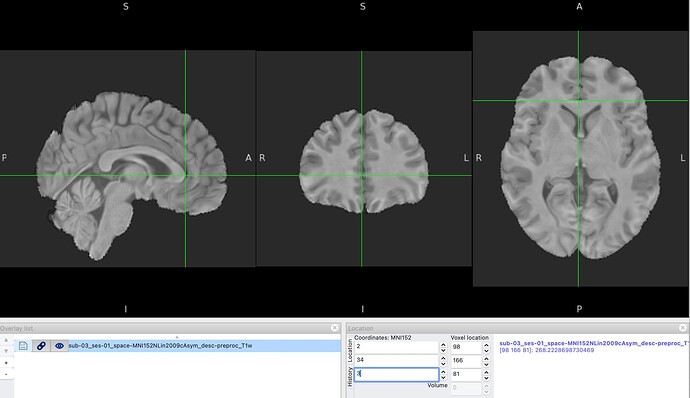

- Choice of parameters in MNI space with FSLeyes, at the genu of the Corpus Calosum:

View of those coordinates on the native image in FSLeyes: